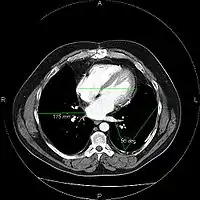

The same image following contrast adjustment, sharpening and measurement tags added by the system

An image as stored on a picture archiving and communication system (PACS)